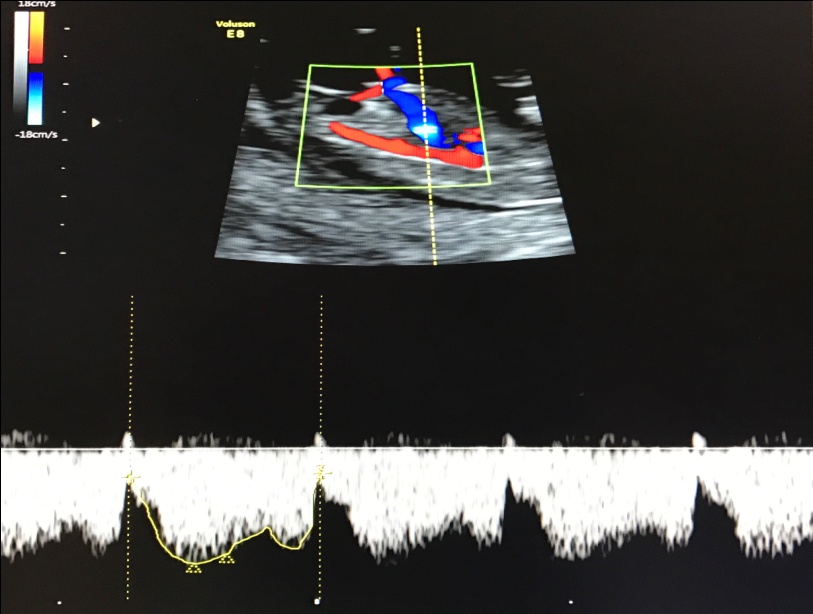

— кровоток в венозном протоке – это маленький сосуд в печени плода. При обратном (ретроградном) токе крови в данном сосуде можно предположить, что у плода хромосомный синдром, либо врожденный порок сердца.

Нормальный кровоток в венозном протоке

Но важно правильно получить этот кровоток и дать ему оценку. Для этого требуются определенные навыки и квалификация врача, которые подтверждаются ежегодной сертификацией FMF.. — кровоток через трикуспидальный клапан в сердце плода